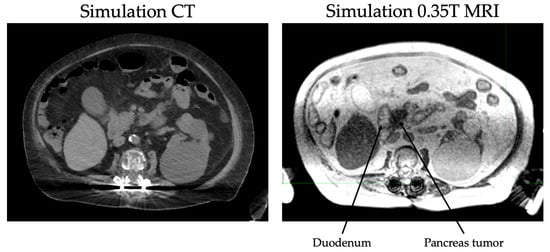

The continuous tracking of tumor volume during treatment also eliminates the need for an ITV or expanded PTV and thus reduces the dose to normal tissue. In pancreatic cancers, daily MR guidance is especially helpful for delineation of the stomach and duodenum from the pancreas (Figure 1). Immobilization devices are not needed due to real time tracking of inter- and intra-fraction motion. Due to superior tracking of both targets and OARs, ablative doses can be prescribed to tumors regardless of proximity to GI structures as compared to CT-based radiotherapy. For example, dose-escalation studies such as Krishnan et al. [21] limited doses to tumors within 1 cm of GI structures due to toxicity concerns. With MRgRT, limitation of the prescription dose is not necessary. Online adaptive planning allows recontouring of relevant structures and recalculation of the dose received by the tumor and OARs with each fraction [31,32,33].

Figure 1. CT vs. MRI at simulation for a patient with pancreas head adenocarcinoma.